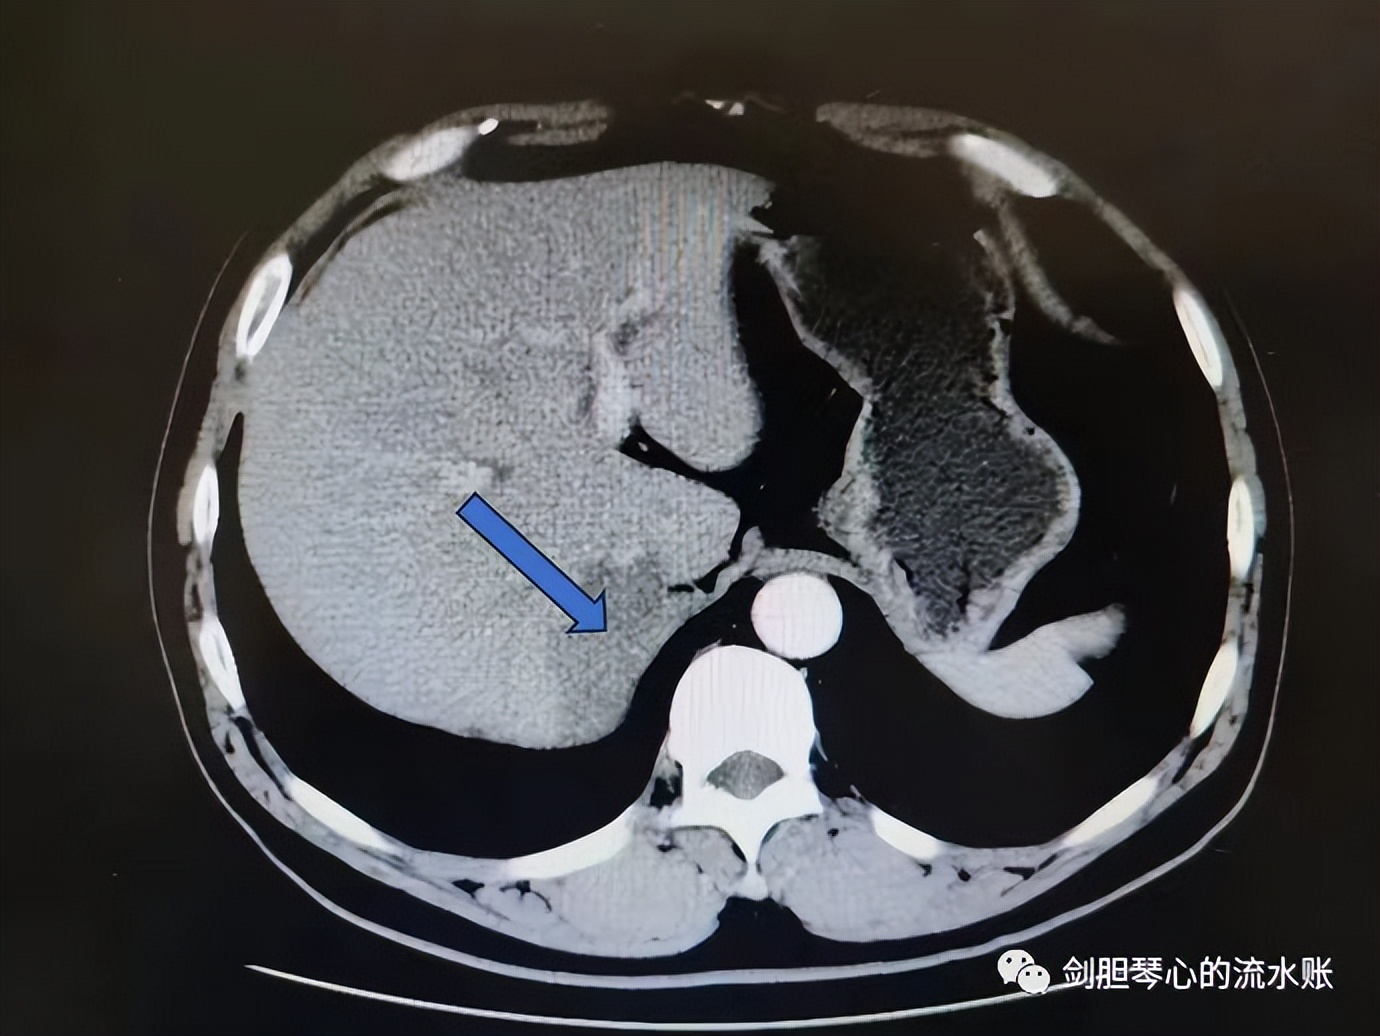

上腹部增强CT:肝右后叶与左侧膈角间异常密度占位,范围约3*5.9cm,边界尚清。